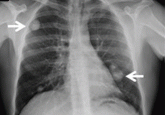

ArticleA farmer with chest pain and lung nodulesAuthor:David Esteva Fernández, MDPublish date: July 1, 2012The patient, age 50, was treated 25 years ago for brucellosis. But he is also a 30-pack-year smoker. What does he have?Read More